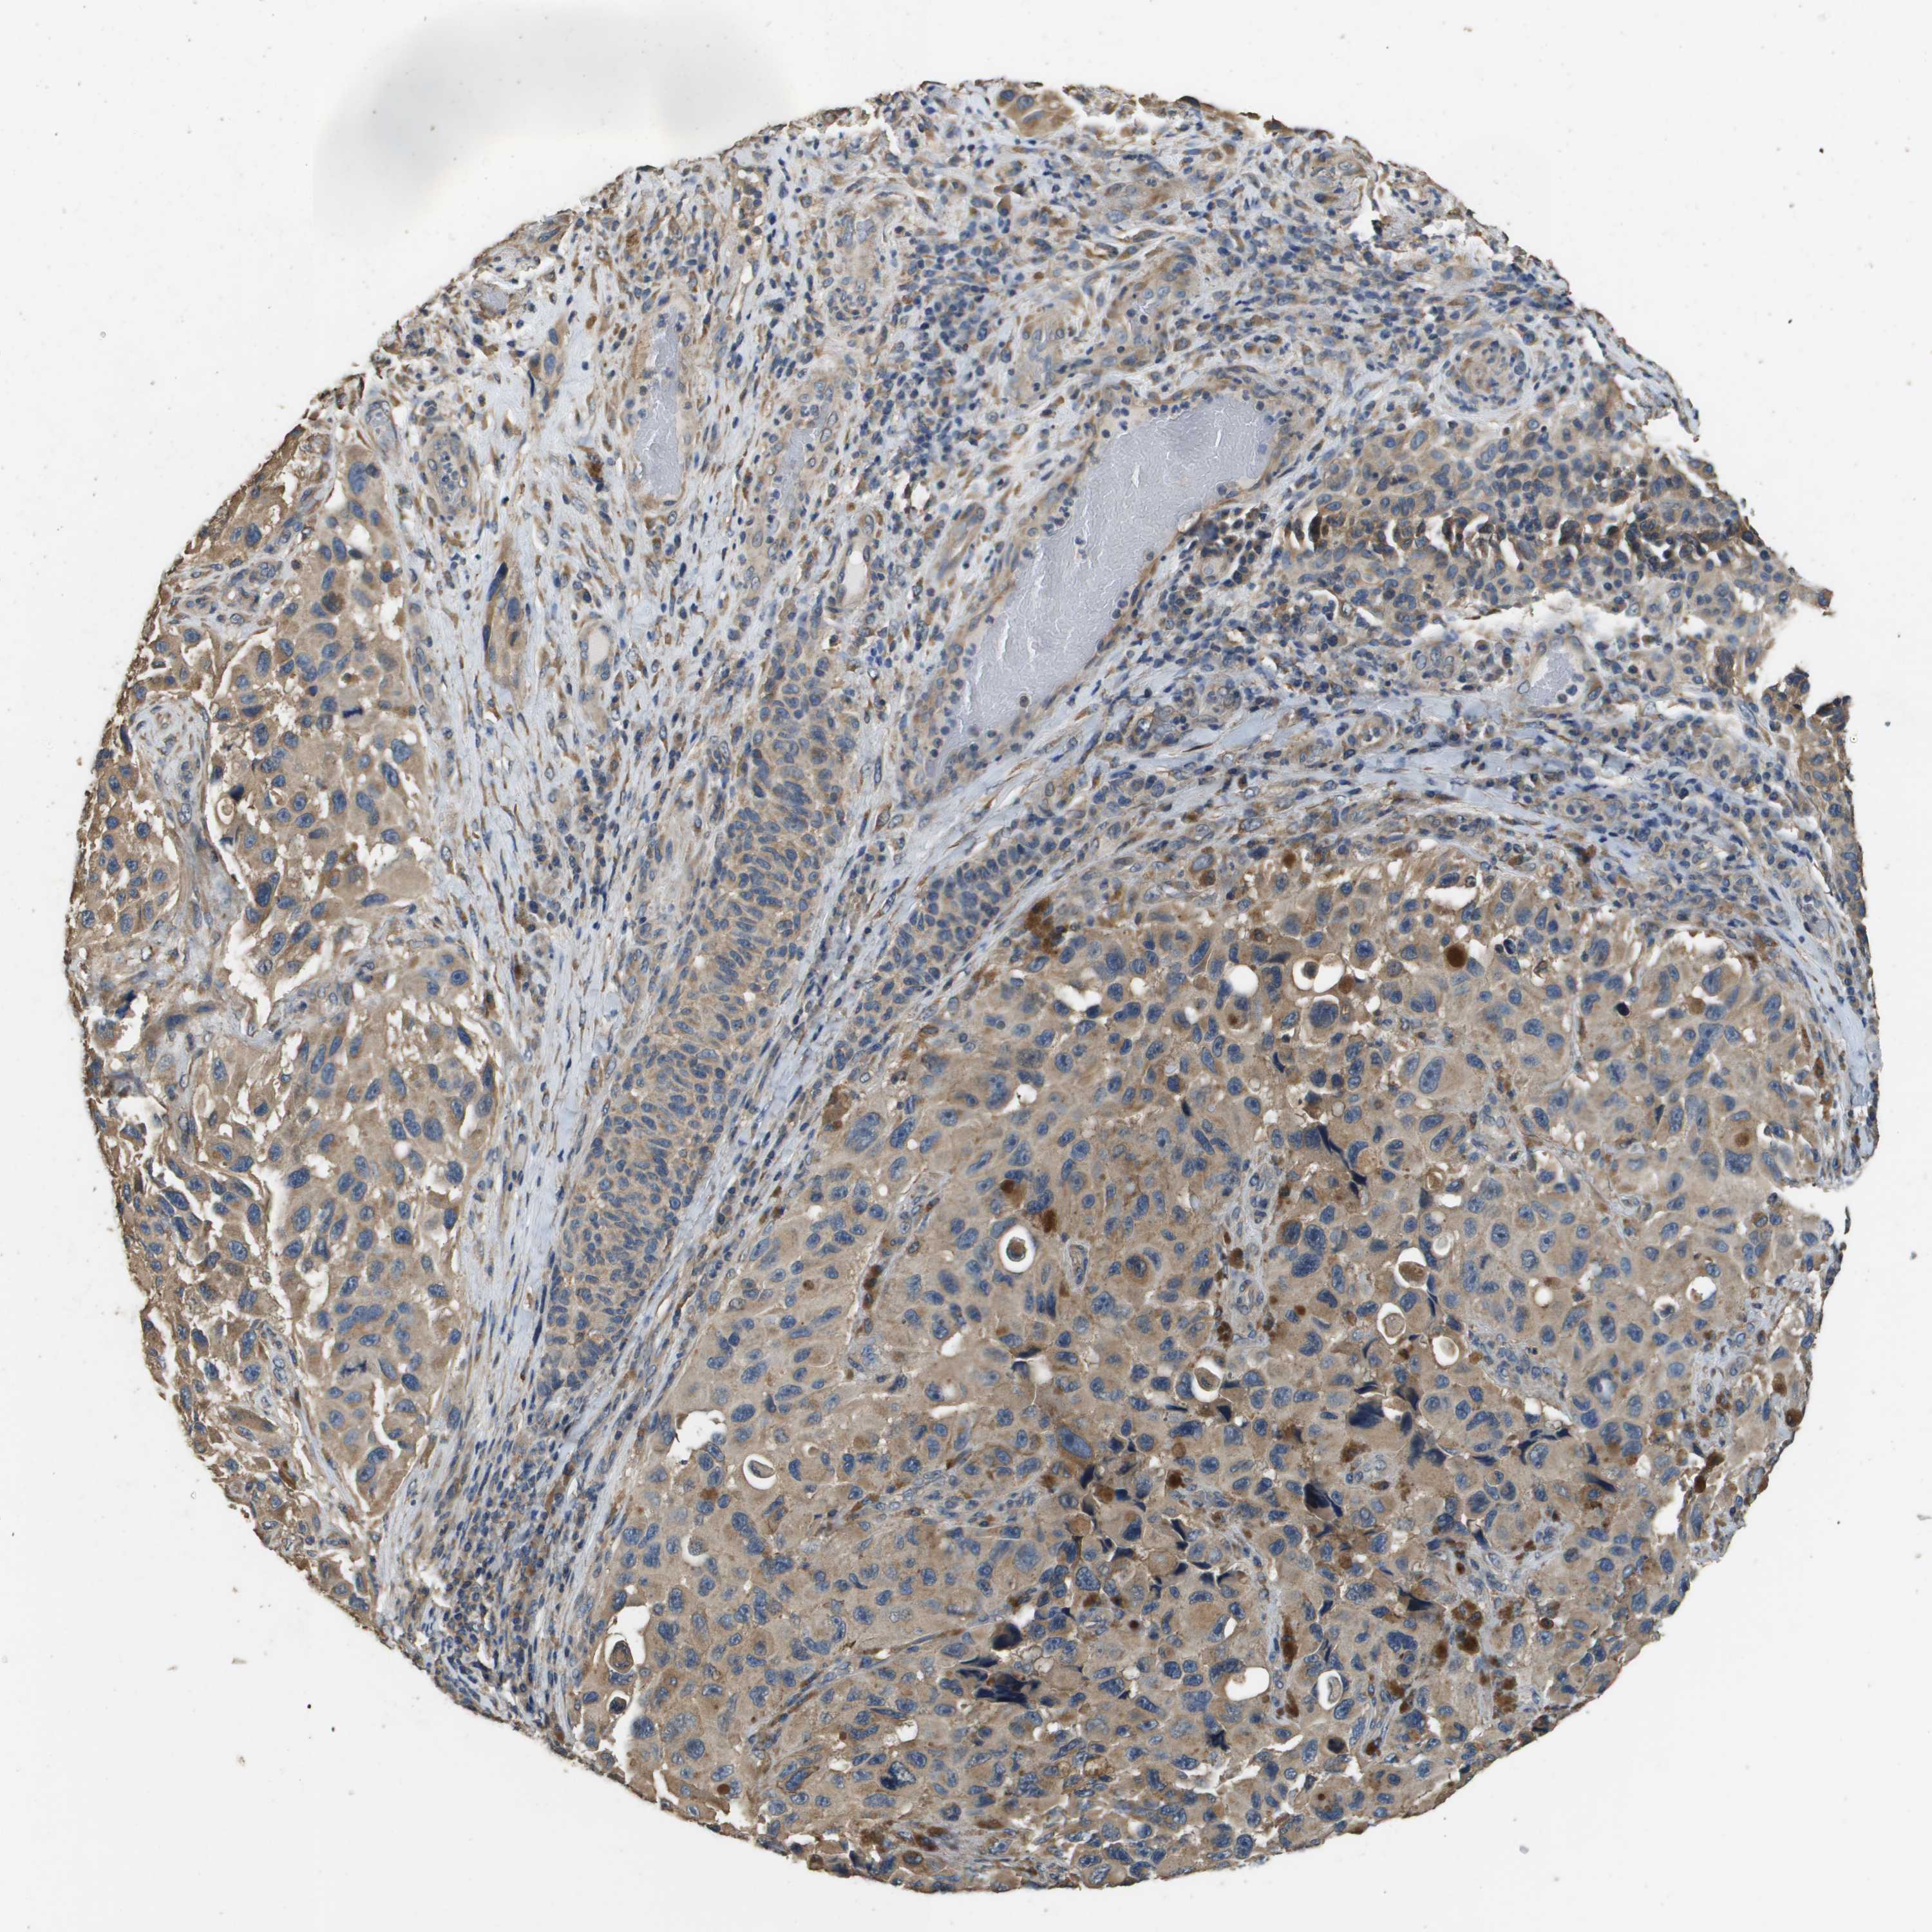

MELANOMA - Protein expressioni

A mouse-over function shows sample information and annotation data. Click on an image to view it in a full screen mode. Samples can be filtered based on level of antibody staining by selecting one or several of the following categories: high, medium, low and not detected. The assay and annotation is described here.

Note that samples used for immunohistochemistry by the Human Protein Atlas do not correspond to samples in the TCGA dataset.

Antibody stainingi

Antibody staining in the annotated cell types in the current human tissue is reported as not detected, low, medium, or high, based on conventional immunohistochemistry profiling in selected tissues. This score is based on the combination of the staining intensity and fraction of stained cells.

Each image is clickable and will lead to virtual microscopy that enables deeper exploration of all samples and also displays staining intensity scores, fraction scores and subcellular localization as well as patient and tissue information for each sample.

Antibody HPA059131

Antibody CAB017713

Staining

High

Medium

Low

Not detected

Intensity

Strong

Moderate

Weak

Negative

Quantity

>75%

75%-25%

<25%

None

Location

Nuclear

Cytoplasmic/membranous

Cytoplasmic/membranous,nuclear

Malignant melanoma, NOS

Malignant melanoma, Metastatic site